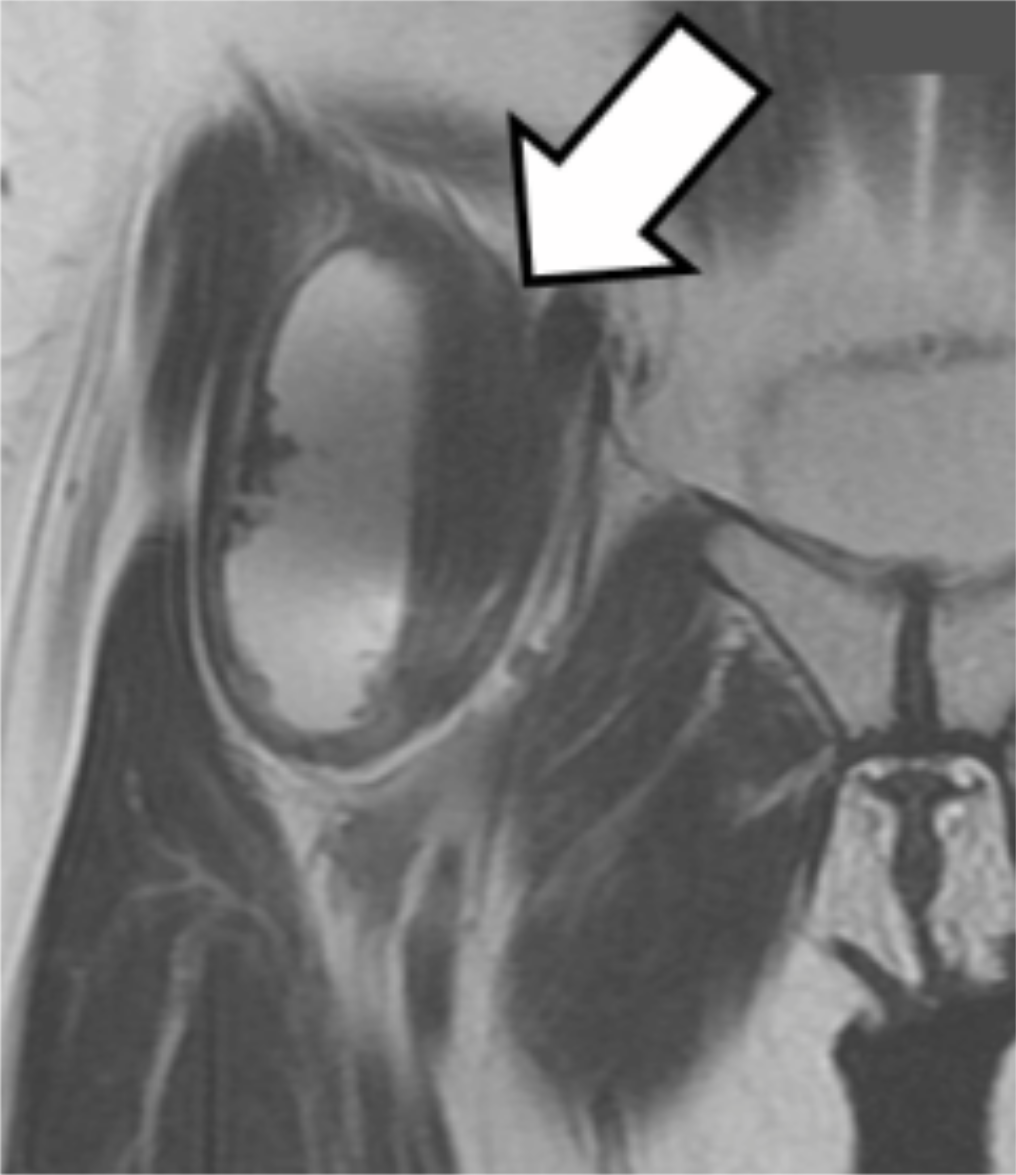

Magnetic resonance imaging (MRI) (Signa HDxt 1.5T Optima Edition GE Healthcare, Tokyo, Japan) demonstrated a large pseudotumor around the anterior hip joint (Figure 3).

Figure 3: T2-weighted coronal MR image in Case 1 (Arrow: pseudotumor).